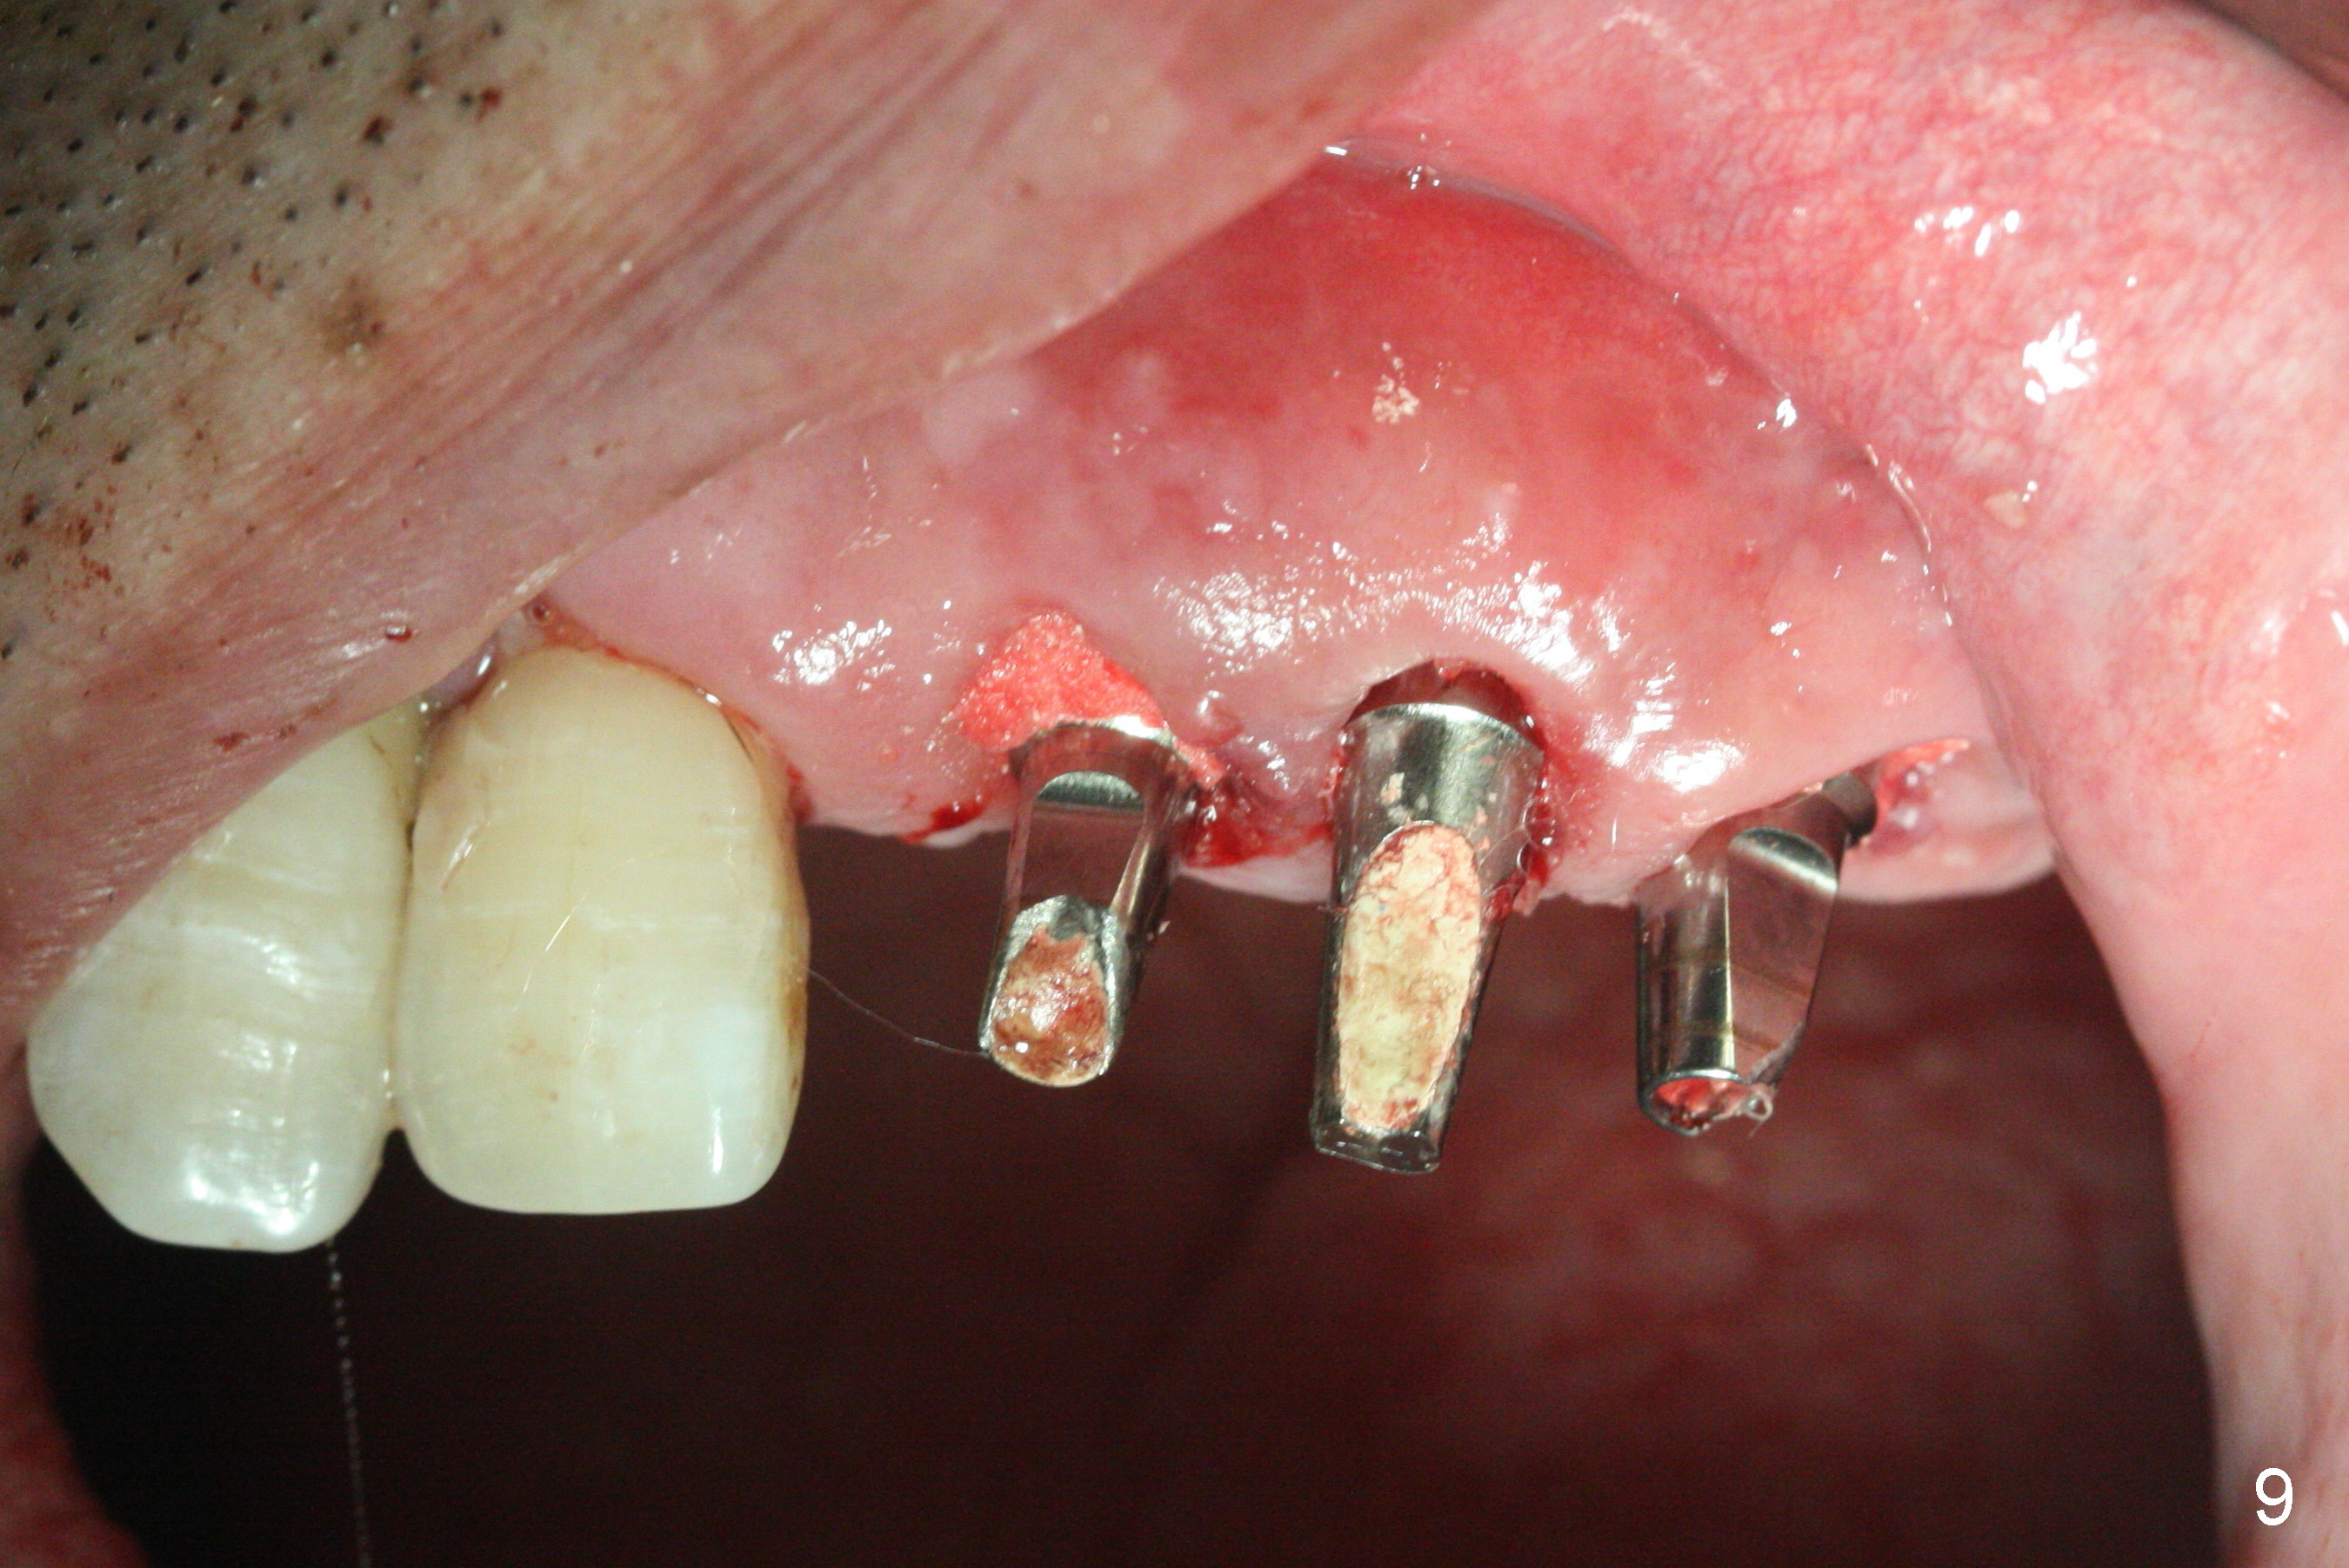

The dentition is poor except #6 and 8 (Fig.1). The gingiva is erythematous at #9-11 (Fig.2). The teeth #9 and 10 are extracted first; a 4x16 mm UF implant is placed at #9, while a 2 mm pilot drill is at the site of #10 (Fig.3). The implant at #9 is placed deeper with placement of 4.5x5.5(5) mm abutment; a 3.8x15 mm implant is placed at #10 initially (Fig.4). While the latter is placed deeper, a 4x16 mm implant is placed at #11 (Fig.5 after removal of #11-15 FPD (fixed partial denture)). In fact the trajectory at #11 is not difficult to be changed with 2 mm drill (Fig.6). After use of 3 mm drill, the implant is reinserted at #11 with ideal trajectory (Fig.7). After further seating of the implant at #11, graft is placed in the remaining sockets of #9-11 (Fig.8 *; later more graft is placed mesial to #11 implant (^)). Finally, a 4.5x7(5), 4.5x15° B (4) and 5.5x7(5) mm abutments are tightened and prepared (Fig.9) for splinted provisional at #9-10.

The patient returns 8 days postop, uncomfortable with overhang in the provisional (Fig.10 *). The sockets appear to be healing with loose bone graft (Fig.11) when the provisional is removed for trimming (Fig.12). Six (for #7,13) and seven (#9-11,15) months postop, the soft (Fig.13,17) and hard (Fig.14-16,18) tissues heal. It appears that the trajectory at #9,11 and 13 should be changed by using angled abutments (Fig.18,19 (panoramic X-ray taken 2 months earlier)) before provisional and final restoration.

In fact angled abutments are used at #11 and 13 (4.5x15 degree (5 mm)A) with a straight abutment at #15 (5.5x4(4) mm).